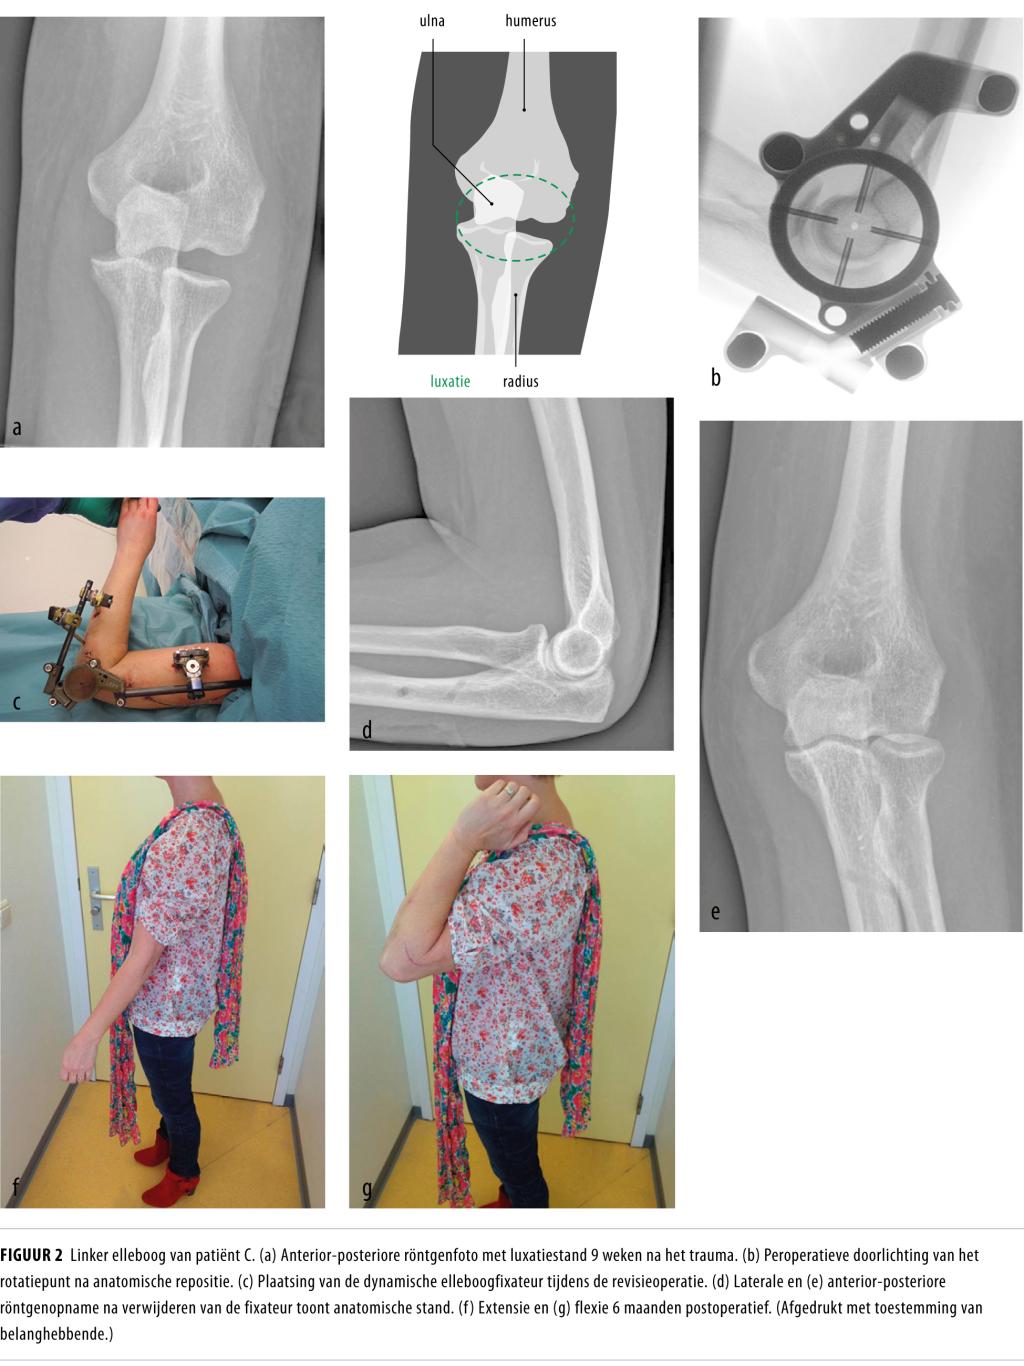

Jaarlijks bezoeken meer dan 1000 mensen in Nederland de Spoedeisende Hulp vanwege een elleboogluxatie na een val op een uitgestrekte arm. We spreken van een simpele elleboogluxatie als er alleen bandletsel is. Een complexe elleboogluxatie gaat gepaard met een begeleidende fractuur, voornamelijk van de radiuskop of proximale ulna. Gipsimmobilisatie na repositie van het ellebooggewricht leidt bij beide typen luxaties tot blijvende, vaak invaliderende functiebeperking. Om deze problemen te voorkomen hebben patiënten met een elleboogluxatie het meeste baat bij een functionele nabehandeling.